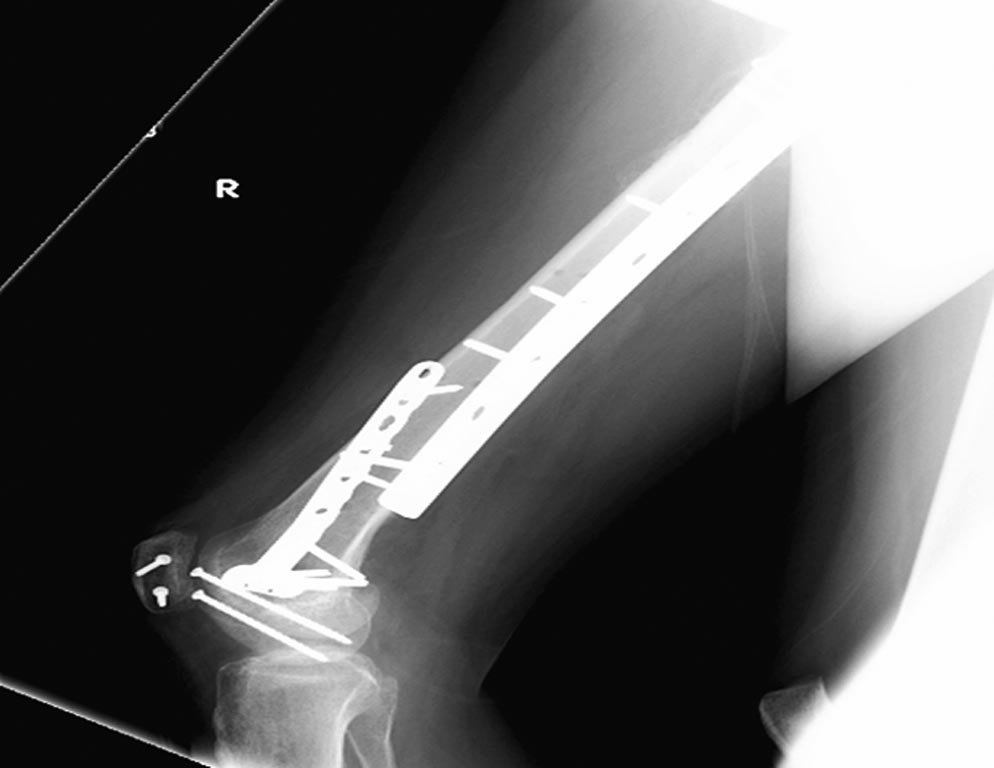

На 25 день с момента травмы операция на Jackson table с боковым обширным

доступом. Удаление стержней с местной обработкой. В тазобедренном

суставе удаление головки, на дне вертлужной впадины полная отслойка

хряща. Вертлужный компонент с одним винтом и короткая ножка -  Fitmore

Выписана. Нагрузку разрешили на левой стороне, а полная в 3 мес.  Здесь

снимки при амбулаторном наблюдении​: послеоперационно, 2 мес, 3 мес и 6

мес. Нагрузка полная, отсутствует хромота, и нет жалоб.